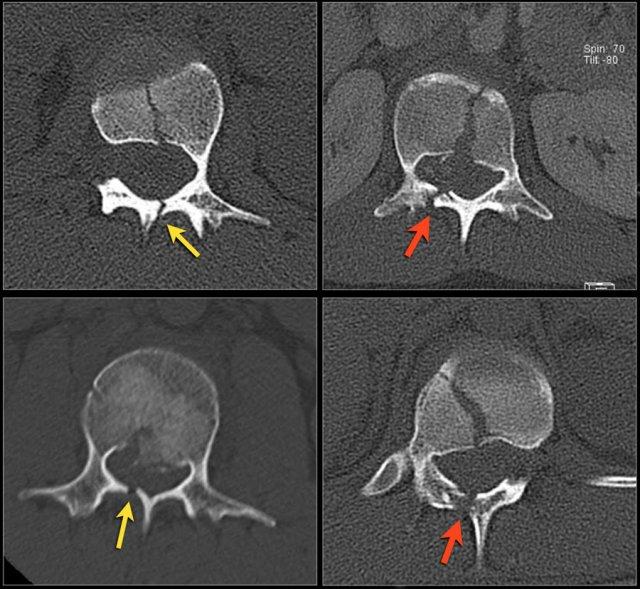

Mảnh xương góc sau trên thân đốt sống bị đẩy lùi ra sau (Retropulsion)

Hiện tượng mảnh xương bị đẩy lùi ra sau là đặc điểm điển hình của gãy vỡ, phân biệt rõ ràng với gãy nén đơn thuần.

Cuộn qua các hình ảnh.

Gãy theo mặt phẳng đứng dọc của thân đốt sống và

cung sau đốt sống

Gãy theo mặt phẳng đứng dọc của thân đốt sống và gãy cung sau theo mặt phẳng đứng dọc gặp lần lượt trong 90% và 85% các trường hợp gãy vỡ.

Dưới đây là bốn ví dụ minh họa.

Trong phân loại Denis, đây sẽ là gãy ba cột — trước/giữa/sau — cho thấy gãy xương rất không vững.

Tuy nhiên, trong phân loại TLICS, đây là gãy vỡ, tức là 2 điểm cho hình thái.

Phương pháp điều trị sẽ phụ thuộc vào tính toàn vẹn của PLC và tình trạng thần kinh.